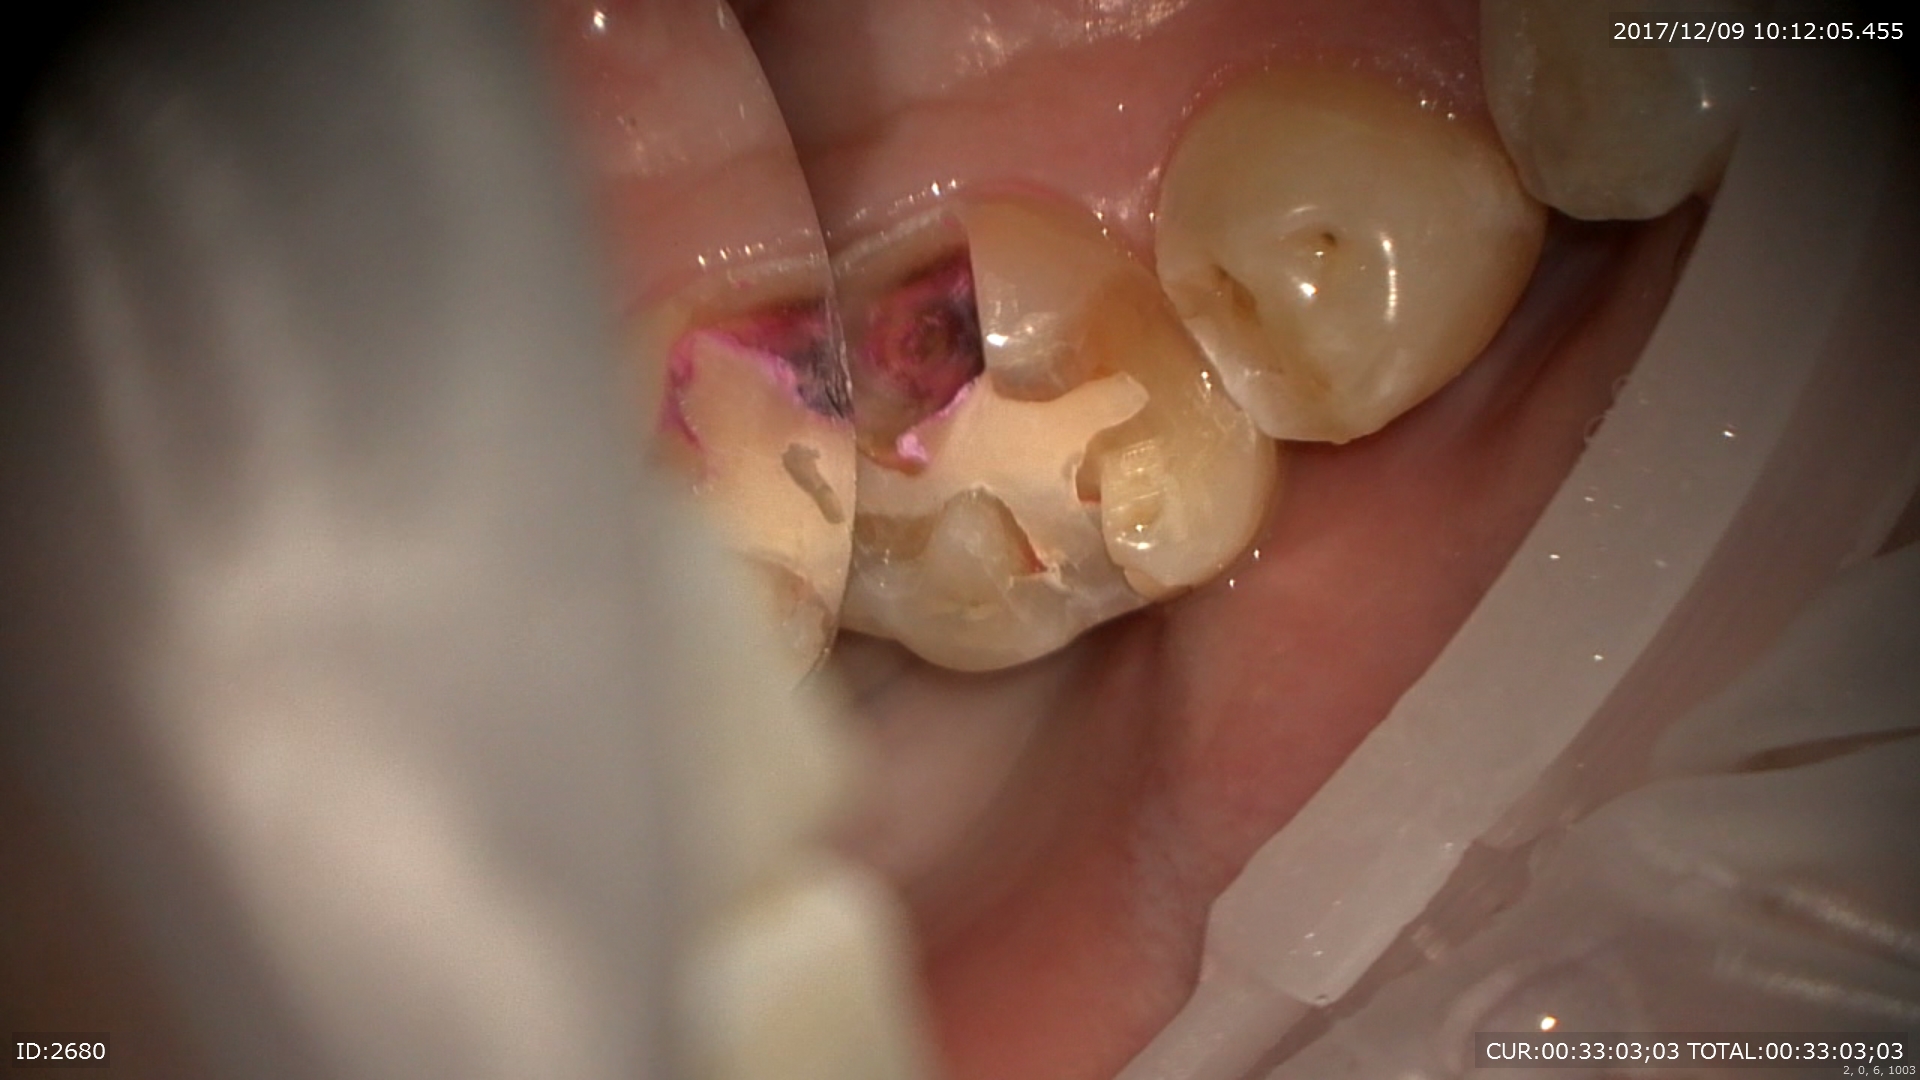

次は虫歯のケース。プラスチックはこのように汚れ(細菌)を寄せ付け二次虫歯を発生させます。

外すと あらま。感染だらけ。マイクロスコープで丁寧に無痛で。

感染を取るとこんなに歯がなくなってしまいます。裸眼でとったら神経見えるかも。。

MTAで神経保護

また神経に優しい治療ができて幸せ!